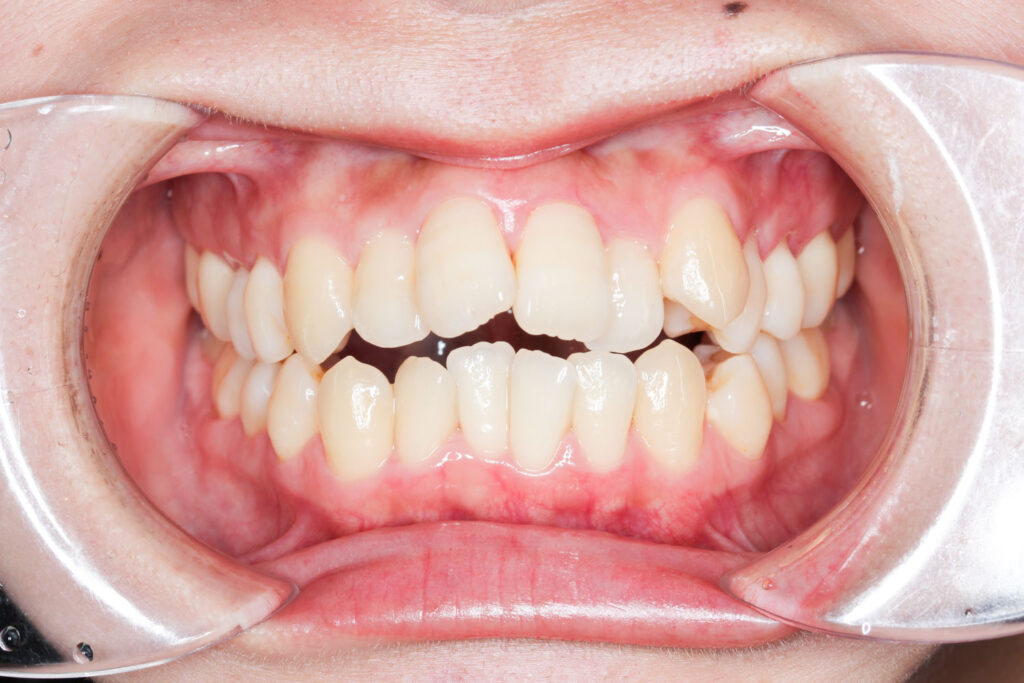

Before

After

年齢 10代

治療装置 上は裏側の矯正装置(ハーフリンガル)

治療内容 上下左右4本抜歯

治療期間 2年8か月

リスク 歯の移動に伴う痛み、歯肉退縮、歯根吸収、歯肉炎、虫歯

主訴 八重歯が気になる

症状 叢生(ガタガタ)

治療回数 33回程度

総額費用 125万円程度